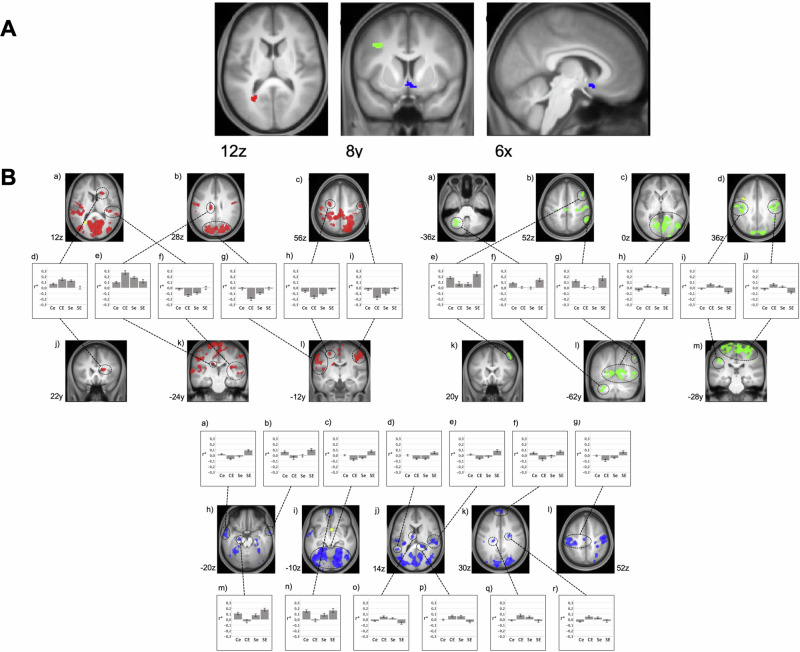

MVPA and post-hoc SCA

In the MVPA, we identified three significant clusters: left calcarine fissure/left precuneus (CAL, MNI: −26x, −60y, 12z, 70 voxels, p(FDR) = 0.002), subgenual anterior cingulate cortex (sACC, MNI: 6x, 10 y, −12z, 65 voxels, p(FDR) = 0.002), and left middle frontal gyrus (MFG, MNI: −34x, 8 y, 36z, 42 voxels, p(FDR) = 0.016).

Post-hoc SCA of these clusters revealed a widespread set of cortical areas exhibiting significant interactions between SAD and ELA. Areas showing altered connectivity with the CAL are located in the visual cortex, medial and lateral pre- and post-central regions, right superior temporal gyrus, left superior and middle frontal gyrus, and bilateral caudate nucleus (Table S4, Fig. 2).

Fig. 2. Multi voxel pattern analysis (MVPA) and post hoc explanatory seed-based correlation analysis (SCA).

RSFC interactions between SAD and ELA. Results are shown at p < 0.001, uncorrected at voxel-level and p < 0.05, FDR-corrected at cluster-level projected onto the mean T1-weighted anatomical scan (n = 120); FDR = false discovery rate. A – MVPA: Red: left calcarine fissure/ precuneus (CAL); green: left middle frontal gyrus (MFG); blue: subgenual anterior cingulate cortex (sACC). B – SCA based on MVPA cluster seeds (yellow): Areas exhibiting an interaction of SAD and ELA with the left calcarine fissure/ precuneus (CAL, red, see Table S4 for details), with the left middle frontal gyrus (MFG, green, see Table S6 for details) and with the subgenual anterior cingulate cortex (sACC, blue, see Table S5 for details). Diagrams depict the observed interaction patterns (Ce: controls with low ELA, CE: controls with high ELA, Se: participants with SAD and low ELA, SE: participants with SAD and high ELA). Z-transformed bivariate correlation coefficients (r*) are given on the y-axis. Error bars represent standard error.

For the sACC, interactions of SAD and ELA are located in the visual cortex, in pre- and postcentral regions, in the middle and superior temporal gyrus, in the middle and superior frontal gyrus, in the left inferior parietal gyrus, as well as in the left hippocampus and thalamus and bilateral caudate nucleus (Table S5, Fig. 2).

The RSFC pattern for the MFG shows such interactions mainly in the visual cortex, pre- and postcentral regions, right middle frontal gyrus, inferior parietal regions and cerebellum (Table S6, Fig. 2).